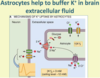

Describe the maintenance of ionic environment role of astrocytes

Maintain ionic environment - extracellular [K+] buffering. A high extracellular K+ concentration around a neuron can result in its depolarisation. Consequently, astrocytes remove K+ ions from the extracellular fluid to keep this ECF concentration low; as a result, astrocytes have a very negative resting membrane potential due to their high intracellular potassium levels. Astrocytes are coupled together by gap junctions.